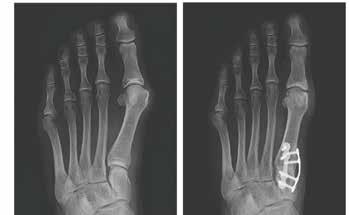

A before and after X-ray of a foot bunion treated with the Lapiplasty procedecure.

Treace Medical was formed to develop and market a procedure to treat bunions called Lapiplasty.

He said Lapiplasty improves on other bunion treatments “by surgically correcting all three planes of the bunion deformity and securing the unstable joint, thereby addressing the root cause of the bunion.”